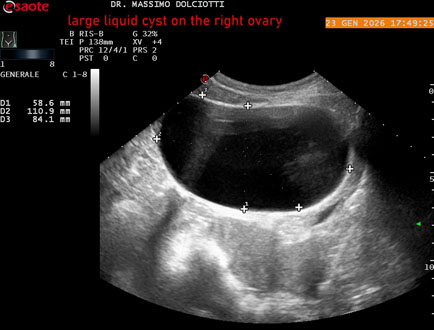

Data inserimento: 26/01/2026

Ecografia del: 23/01/2025

Strumento: Esaote MyLab Eight

Sonda: Conevx Multifrequenza 1-8 MHz

Età Paziente: F 29 anni

Motivazione dell'esame: dolore al lato destro della pelvi in portarice di cisti liquida all'ovaio destro.

Commento all'esame: le immagini ed il video documentano, in sede pelvica, grande formazione anecogena, delle dimensioni di 110 x 60 mm, priva di vascolarizzazione, da ricondurre a grande cisti liquida dell'ovaio destro.

Conclusioni: grande cisti liquida all'ovaio destro (large fluid cyst on the right ovary).

In collaborazione: Dr.ssa Marica Manfredi - Ancona, Dr. Ilir Qose - Ancona

Presentazione: Dr. Massimo Dolciotti - Ancona

Elaborazione digitale: Andrea Dini - Ancona